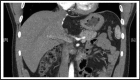

The majority of giant hepatic cavernous hemangiomas are asymptomatic and can safely be observed. However, when a lesion becomes symptomatic, affecting quality of life or cannot be distinguished from a malignancy, then operative therapy should be considered. We herein present a case of a symptomatic 12cm × 14cm × 17cm "mega" hemangioma (>10cm) of the left hepatic lobe. This lesion was initially refractory to transarterial embolization of the left hepatic artery, but was subsequently treated successfully with a left lateral extended hepatic segmentectomy (resection). We thus advocate a rational treatment algorithm for management of hepatic "mega" hemangiomas.